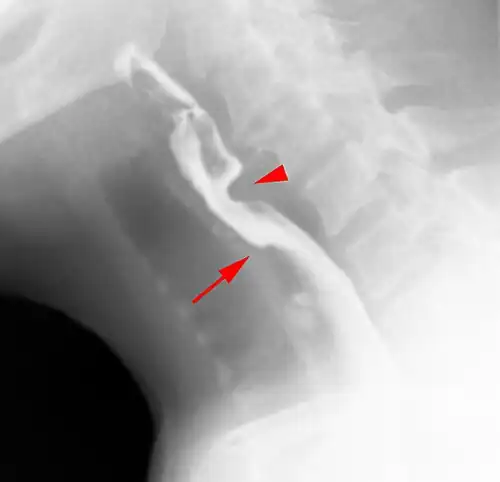

Esophageal web stenosis in barium swallow examination lateral view. -

Web with "jet-phenomenon". Arrowhead on incomplete opening of the upper esophageal sphincter. -